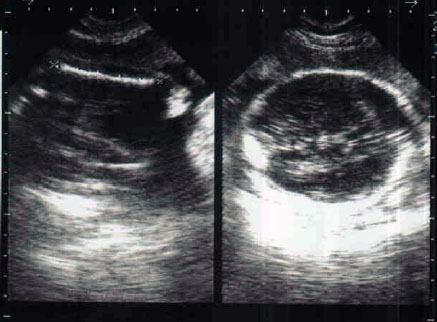

Attachment 3130

Attachment 3131